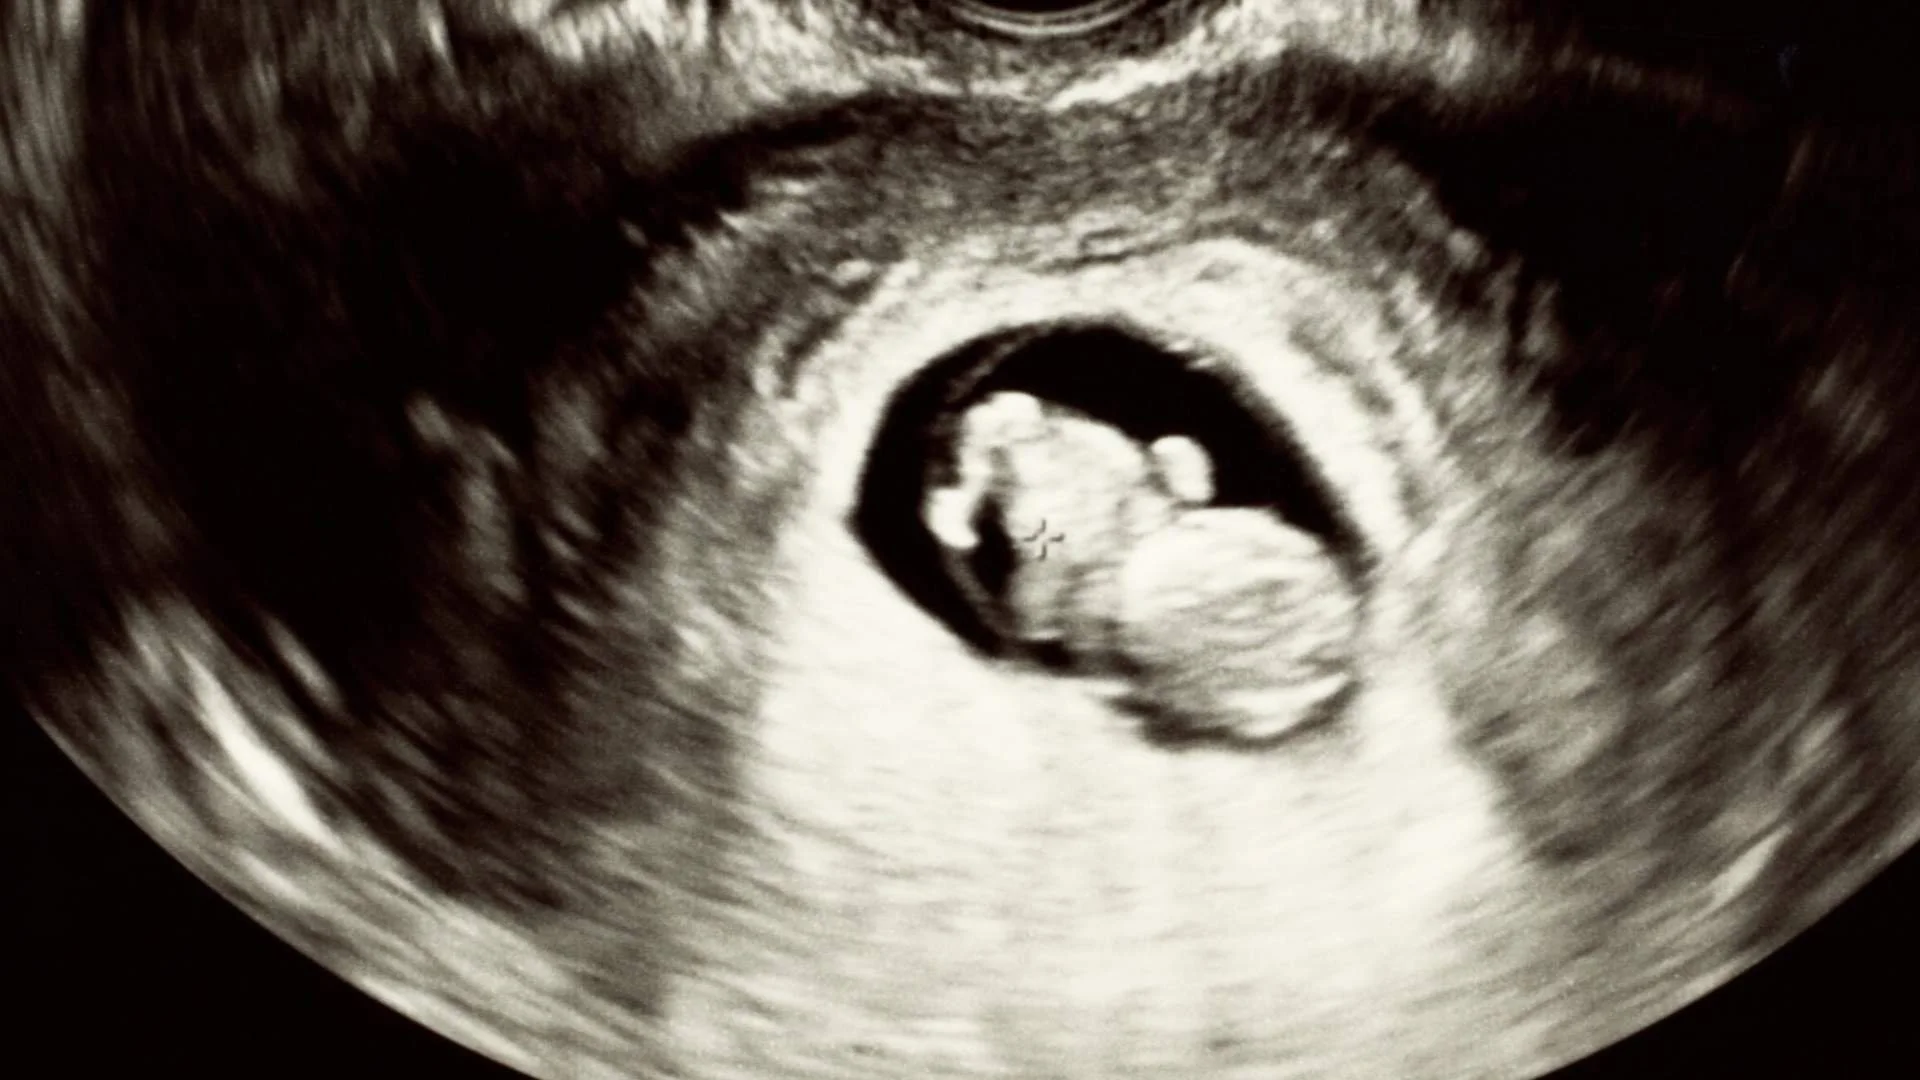

During pregnancy, the placenta plays a vital role in supporting your baby’s growth, supplying oxygen and nutrients throughout the journey. In some pregnancies, the placenta lies lower than usual in the uterus, sometimes covering the cervix. This is known as placenta previa or a low-lying placenta. While this can sound concerning, careful monitoring and planning usually lead to safe outcomes for both mother and baby.

This condition is usually identified during a routine ultrasound at 18–20 weeks, known as the morphology scan. Most of the time, the placenta naturally moves upward as the uterus grows, resolving before the later stages of pregnancy.